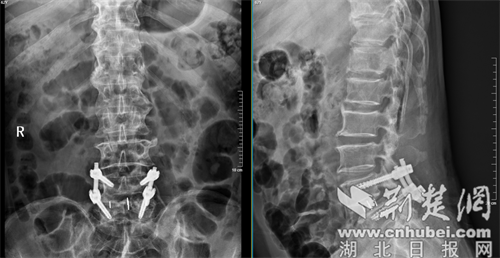

该技术通过人体腹侧肌肉的天然解剖间隙到达病变的椎间盘,不损伤腰椎后方的肌肉、韧带和骨骼结构。在麻醉科和手术室的密切配合下,主刀医生借助导航精准定位,沿腹侧外侧切口,逐层显露,精准放置通道,彻底摘除退变的髓核组织,处理好终板后,植入了填充了自体骨和异体骨的椎间融合器。术后透视显示,融合器位置理想,椎间隙高度恢复良好。

术后检测报告。通讯员 供图